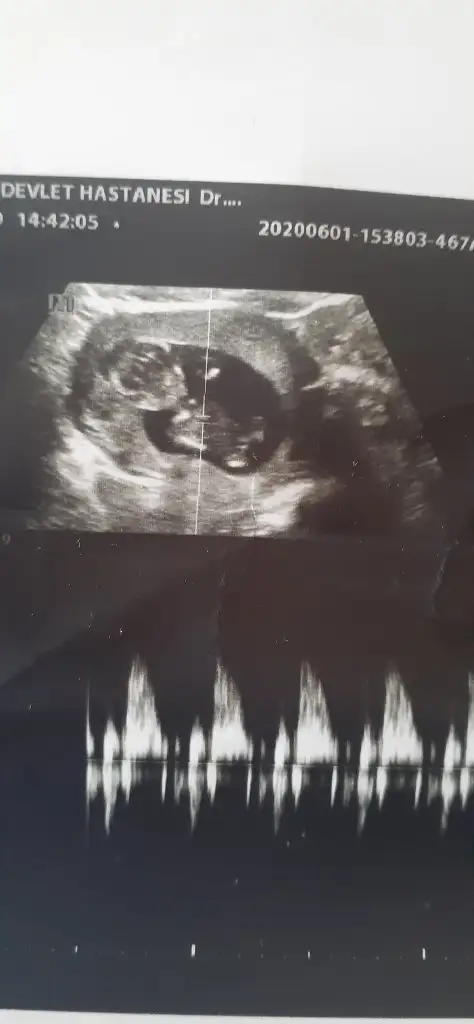

Burda 11 haftalık teşekkür ediyorum

Erkek gibiBuda benim bebeğim eğer bakarsanız sevinirim Allahım sağlıkla versin kucaklarımıza merak etim 3 hafta sonra öğreneceğiz cinsiyetini şimdiden teşekkür ediyorum

Erkek gibi